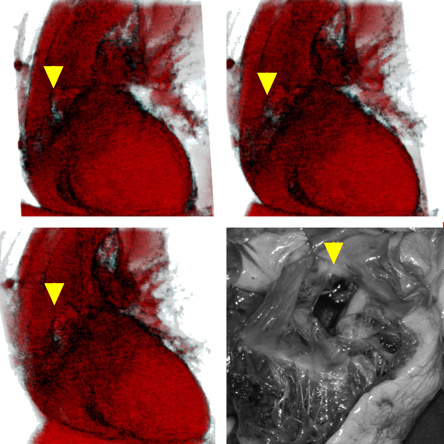

Part of my initial work within this project dealt with visualising cardiac pathology of forensic relevance. While it was still news to say that such a perforating laceration of the base of the heart could not be easily found on CT or MR images (see above citation – poster for San Diego), it became then news to say that it is possible to visualise this laceration. The company selling IDL in Germany, Switzerland and Austria (Creaso in Gilching out of Munich, Germany) also thought this was good news on their (now defunct) news page.

The soft tissue defect shown in the 3D renderings based on CT scans (yellow arrows; Software: IDL 5.4 on a PowerMac G4 / 867 MHz – http://www.rsinc.com, http://www.apple.com) differs in appearance compared to the autopsy finding particularly due to non-invasive data acquisition being non-dynamic, whereas autopsy handling dynamically compresses, stretches or distends soft tissue.